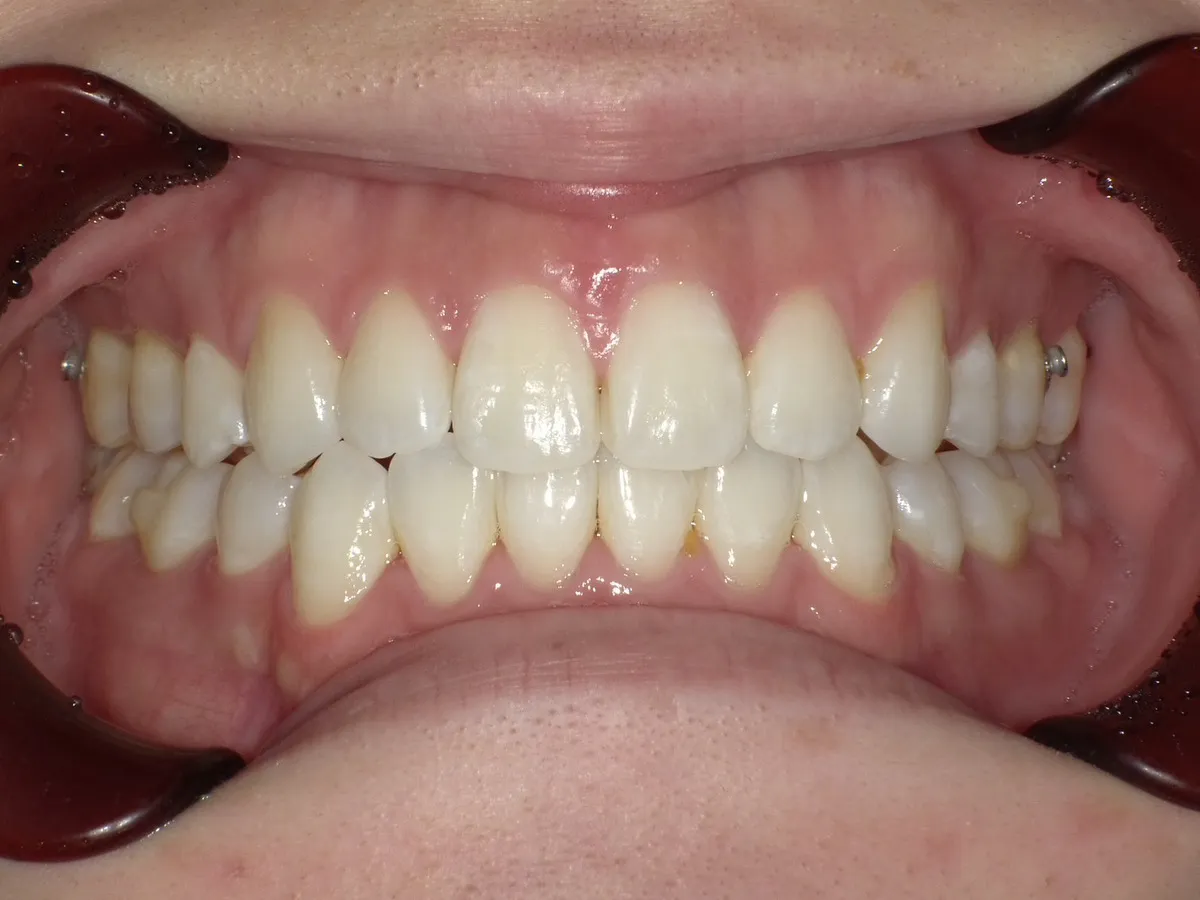

症例⑦

症例8_治療前 症例8_治療後

年齢・性別 18才・女性

治療方法 ブラケット矯正

治療期間 3年

治療総額 825,000円

特記事項 4本抜歯